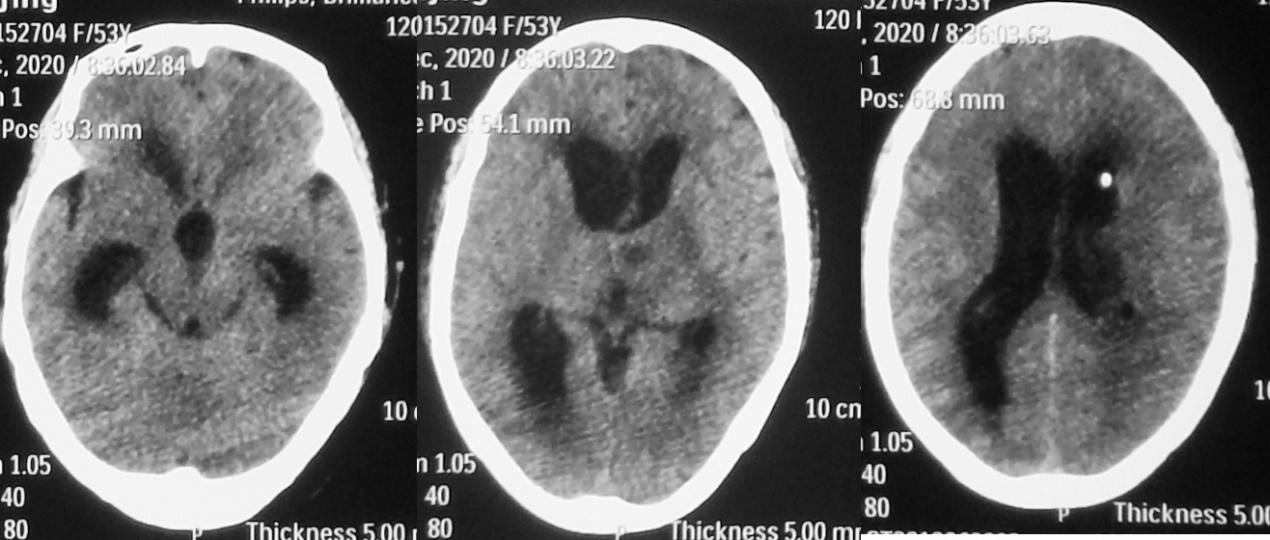

发病后24天,抗炎及脑室外引流治疗后11天,即2020年12月2日,精神仍差,间断发热,体温38℃左右,复查头颅增强核磁( 图-7 )见左侧丘脑脓肿病灶环形强化,同时左侧脑室枕角及小脑表面可见强化(感染),提示感染较前范围扩大。

图-7: 2020年12月2日头增强核磁